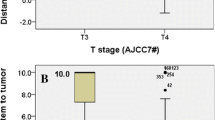

A total of 8 cases (8/327) developed MRI-indicated radiotherapy-induced brainstem injury. The actuarial incidence rates were 2.2% and 2.8% at 3 and 5 years, respectively; and these were 2.5% and 5.3% in T3 and T4 patients, respectively (Fig. 1). The median latency period was 21 months (range, 9–58 months).

The T category (T4 vs T1–3) as well as GTVnx D2%, Dmax, D1%, D0.1cc, and D1cc of the brainstem were predictive factors of the radiation-induced brainstem injury in Cox regression models (p < 0.05) (Table 2). However, year, sex, N stage, GTVnx D98%, chemotherapy, anteroposterior diameter of the pons cistern, and Dmean were not independent risk factors of radiation-induced brainstem injury.

Five qualitative variables of the predictive factors were also demonstrated by ROC curves for brainstem injury (area under the ROC curves, Table 3); the cutoff points for the dose tolerance for brainstem injury for each parameter were selected using P < 0.05 and Youden’s index. The parameters and cutoff values are shown in Table 4. A cumulative DVH for the dose tolerance of brainstem injury was drawn using the cutoff values (Fig. 3). The curves showed an increasing probability of brainstem injury with increasing dose; based on Fig. 3, it would be appropriate to propose a GTVnx D2% of 77.26 Gy, Dmax of 67.85 Gy, D1% of 60.13 Gy, D0.1cc of 60.75 Gy, and D1cc of 54.58 Gy as the cutoff values for radiation-induced brainstem injury.

Receiver operating characteristic (ROC) curve for D2% of gross tumor volume of nasopharyngeal primary lesions and their direct extensions (GTVnx D2%) (a) and Dmax (b), D1% (c), D0.1 cc (d), and D1cc (e) of the brainstem, respectively. The cutoff points for the five parameters (as the brainstem dose tolerance) were determined to be 77.26 Gy, 67.85 Gy, 60.13 Gy, 60.75 Gy, and 54.58 Gy for NPC patients treated with IMRT. D2%, near the maximum absorbed dose of GTVnx; Dmax, the maximum point dose of brainstem; D1%, the dose of 1% of the brainstem volume; D0.1 cc, the maximum dose of brainstem delivered to a volume of 0.1 ml; D1cc, the maximum dose of brainstem delivered to a volume of 1.0 ml